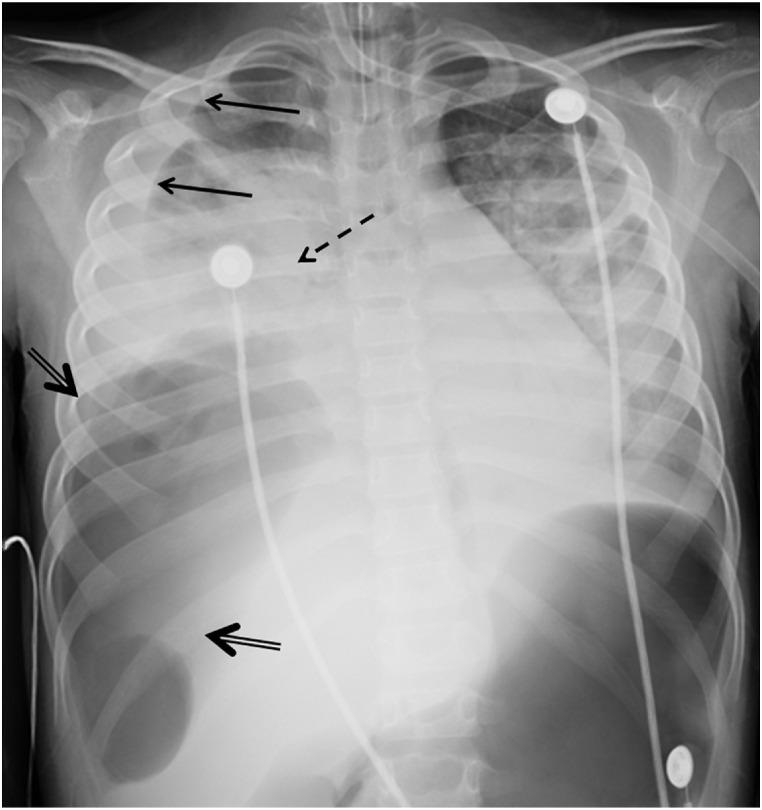

Hypoxic respiratory failure in acute appendicitis: A bronchoperitoneal fistula as the presenting symptom of appendicitis in the setting of pediatric COVID-19.

Symptomatic COVID-19 less frequently affects the pediatric population and is often associated with atypical presenting symptoms. Here we describe a nine-year-old patient who presented with acute hypoxic respiratory failure and was found to have perforated appendicitis, intra-abdominal abscess, and bronchoperitoneal fistula. The rapid progression of this pathology, complex critical care decision making, and ultimate surgical management has not been previously described. Documenting this patient's clinical course and effective treatments may serve to inform and guide the medical community and pediatric care providers as the world continues to combat the COVID-19 pandemic.

有症状的新冠病毒病(COVID-19)较少影响儿童群体,且常伴有非典型的症状表现。在此,我们描述一名9岁患者,该患者出现急性低氧性呼吸衰竭,经检查发现患有阑尾穿孔、腹腔脓肿和支气管腹膜瘘。此前尚未有关于这种病情快速进展、复杂的重症监护决策以及最终手术治疗的描述。记录该患者的临床病程及有效治疗方法,可能有助于在全球继续抗击COVID-19大流行之际,为医学界和儿科护理人员提供信息并给予指导。